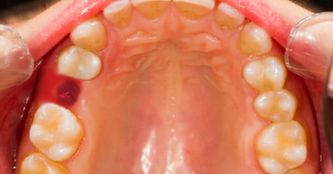

Гингивит обладает основным признаком, по которому он легко определяется, — воспалением, поражающим дёсны ребёнка. Начинается процесс с небольшого покраснения, быстро набирающего силу. Этот сигнал зачастую остаётся незамеченным родителями, и дети попадают к стоматологу уже с активным воспалительным процессом, ярко-красными отёчными дёснами, жжением, болью. Эти признаки говорят, что болезнь вступила в острую фазу.

Дети больше всего страдают от катаральной формы этого недуга, которая бывает хронической или острой. В первом случае симптомы не ярко выражены, боль возникает лишь при чистке, есть небольшая отёчность, покраснение, синюшность дёсен.

В период полового созревания подростка или при наличии у него проблем с гормонами наблюдается гипертрофический гингивит. Он возникает из-за неправильного ортодонтического лечения зубочелюстных аномалий. Воспалительный процесс при этом сопровождается усиленным ростом десневой ткани, что приводит к частичному закрытию зубных коронок. Эта форма болезни обычно носит локализованный характер. Захватывается одна десна или две, иногда участок поражения расширяется. Местом локализации чаще всего становятся передние нижние резцы и клыки.